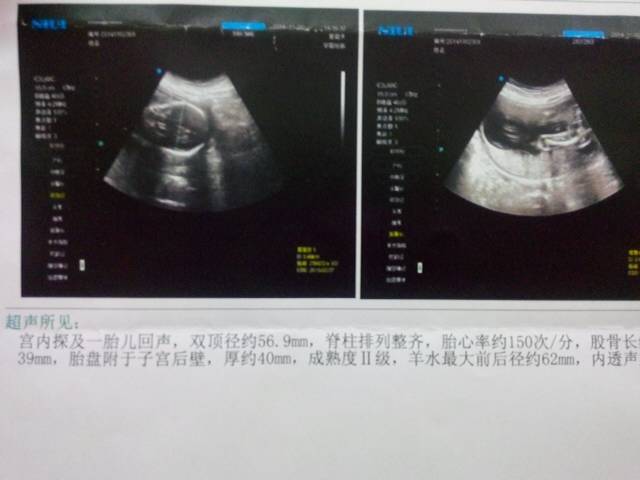

宝妈们帮我看一下今天照的彩超是男宝宝还是女宝宝(5个月)

你所提示的检查结果是看不出男女的,要顺其自然,男女一样。孕期主要是增加全面的营养,保持良好的心情,合理的饮食,多吃瓜果和蔬菜,粗细搭配,安心养胎。